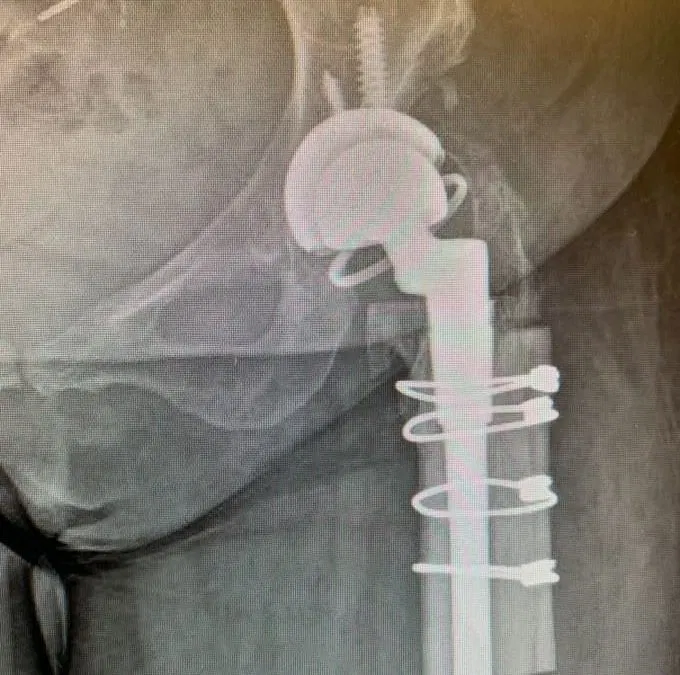

Case Study of Periprosthetic Fracture

Case Study of Periprosthetic Fracture Patient is a 65 year old female that came in about 1 year after having a right Total Hip Arthroplasty (THA) and presented with a displaced femur fracture. Patient required an Open Reduction Internal Fixation (ORIF) procedure to heal the fracture. Due to the patient’s...